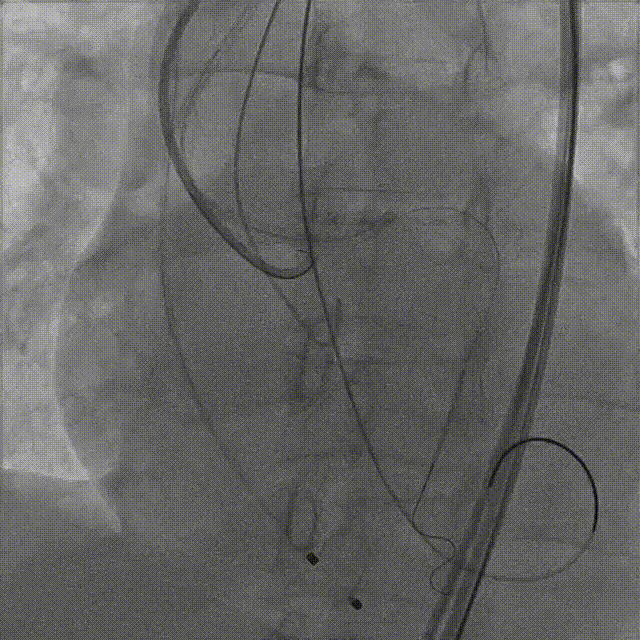

手术过程概览

1.主动脉根部造影

2.18mm球囊预扩

3.左冠造影

4.左冠行支架保护

5.右冠行支架保护

6.右冠造影

7.输送器过弓

8.瓣膜定位

9. 工作位评估冠脉

10.右冠行烟囱支架技术

11.左冠造影评估灌注正常,

撤出支架

12.术后造影